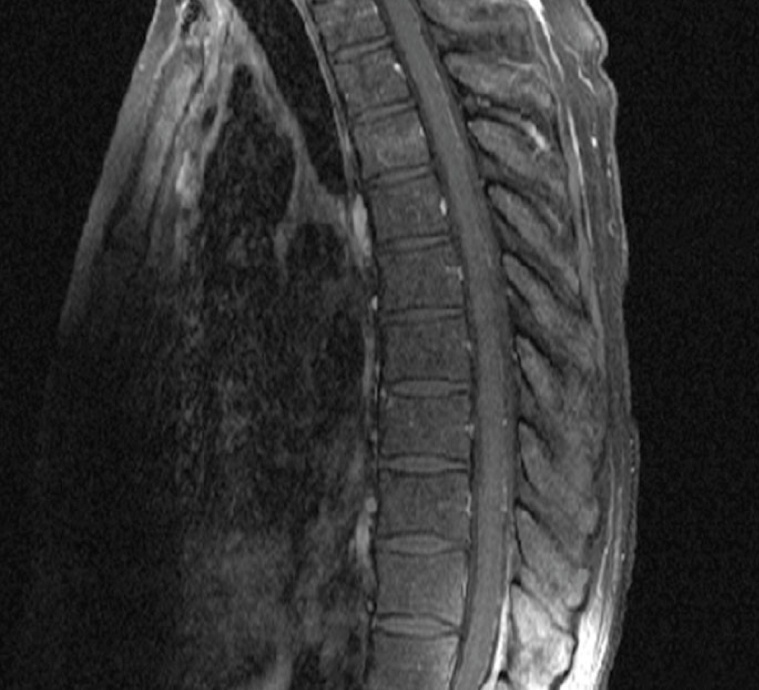

Spinal epidural abscess (SEA) is a rare infection of the epidural space that may threaten the spinal cord and result in paralysis. Most cases are due to hematologic spread from a distant infection (eg, cellulitis, bone/joint), intravenous drug use, or direct inoculation during a spinal procedure. Staphylococcus aureus is the most common (65%) causative organism.

SEA classically results in the triad of fever, back pain, and neurologic deficits; however, all 3 symptoms are present in a minority of cases. Most patients initially develop severe, focal back pain that progresses over days to nerve root pain ("shooting/electric") and more severe neurologic manifestations (motor weakness, sensory changes, bowel/bladder dysfunction, paralysis). The diagnostic test of choice is MRI of the spine due to high sensitivity early in the course of illness and excellent localization of infection extent. Treatment with broad- spectrum antibiotics and aspiration/surgical decompression is usually required.

case: A 68-year-old hospitalized man is evaluated for new-onset leg weakness. Six days ago, he was admitted to the hospital due to fever, right leg pain, and swelling. Physical examination showed right lower extremity edema, erythema, warmth, and tenderness from the foot to the midcalf. Leukocyte count was 16,000/mm3, and venous Doppler ultrasonography revealed patent leg veins without thrombosis. Blood cultures grew Staphylococcus aureus. The patient was treated with intravenous antibiotics, and his leg symptoms improved. However, this morning he had trouble getting out of bed due to significant leg weakness. The patient has a history of hypertension, type 2 diabetes mellitus, coronary artery disease, and systolic heart failure. He also has chronic low back pain from a work-related injury. The patient has had worsening mid-back pain over the last 2 days. Temperature is 38 C (100.4 F), blood pressure is 130/80 mm Hg, and pulse is 88/min. Physical examination shows normal mental status and cranial nerves. Abdominal examination reveals a suprapubic mass. There is midline tenderness over the lower thoracic vertebral area. Upper extremity strength is normal, but he is not able to lift either lower extremity against gravity. Which of the following is the best next step in management of this patient?